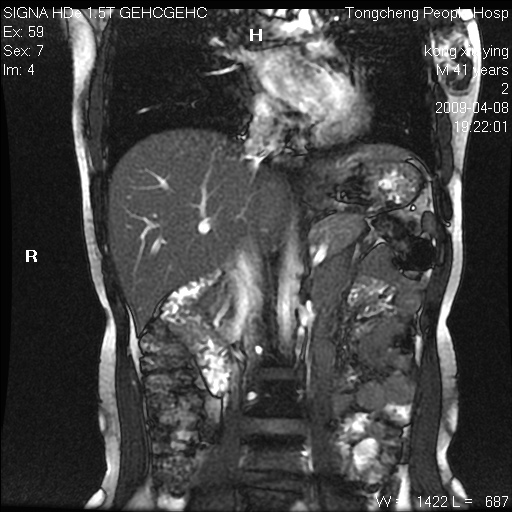

标题: CL1008:【经典】胆囊石榴籽样结石。

女,41岁。健康体检——彩超提示:胆囊显示不清。平素健康,无不适感。

腹部mr扫描及mrcp,图像如下: